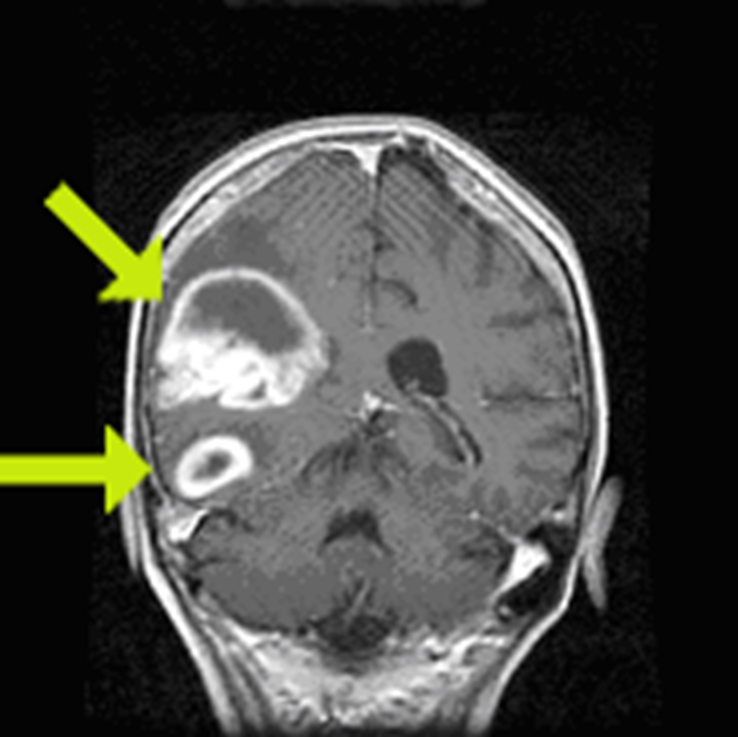

Peak incidence 50-60 years

Neoplasm occupies both hemispheres through the corpus callosum

Irregular ring enhancing

Average 1 year survival

GBM

astrocytoma who grade 4

ring enhancing T1

crosses corpus callosum

necrosis in the middle

(This pattern could be GBM, abccess with correct picture of infection ,or primary CNS lymphoma, but most likely GBM)

Butterfly lesion

astrocytoma grade 4